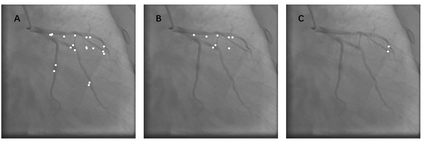

Automatic identification of proper image frames at the end-diastolic (ED) and end-systolic (ES) frames during the review of invasive coronary angiograms (ICA) is important to assess blood flow during a cardiac cycle, reconstruct the 3D arterial anatomy from bi-planar views, and generate the complementary fusion map with myocardial images. The current identification method primarily relies on visual interpretation, making it not only time-consuming but also less reproducible. In this paper, we propose a new method to automatically identify angiographic image frames associated with the ED and ES cardiac phases by using the trajectories of key vessel points (i.e. landmarks). More specifically, a detection algorithm is first used to detect the key points of coronary arteries, and then an optical flow method is employed to track the trajectories of the selected key points. The ED and ES frames are identified based on all these trajectories. Our method was tested with 62 ICA videos from two separate medical centers (22 and 9 patients in sites 1 and 2, respectively). Comparing consensus interpretations by two human expert readers, excellent agreement was achieved by the proposed algorithm: the agreement rates within a one-frame range were 92.99% and 92.73% for the automatic identification of the ED and ES image frames, respectively. In conclusion, the proposed automated method showed great potential for being an integral part of automated ICA image analysis.